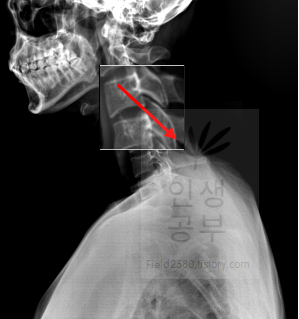

선 긋기를 이용해서 Cobb각을 그린다고 가정했을 때 측정하려고 하는 곳을 처음에 누르고 드래그로 쭉 끌어다주면 위와 같은 선이 생기고 선의 길이가 자동으로 측정됩니다. 첫 번째 목뼈(C1) 선을 그리기 위해 제일 튀어나온 앞쪽 부분 가운데 지점에(Center of Anterior arch) 점을 찍어줍니다. 후궁(Posterior arch) 제일 좁은 부위 가운데 지점에 점을 찍어줍니다. 두 점을 연결해주는 선을 그어줍니다. 이 선 이름을 고리 뼈 선(APL : Atlas Plane Line)이라고 합니다. 점은 조금 더 정확하기 위해서 하는 것이 찍어도 되고, 점을 찍지 않은 상태에서 선을 그으셔도 무방합니다.

일곱번째 목뼈 추체 밑면(Inferior endplate of C7)과 평행한 선을 그어줍니다.

위쪽에 있는 선은 첫 번째 목뼈(C1) 선을 그리기 위해 제일 튀어나온 앞쪽 부분 가운데 지점에(Center of Anterior arch)에서 시작해서 후궁(Posterior arch) 제일 좁은 부위 가운데를 지나는 선이 되도록 이동해줍니다. 선 이름을 고리 뼈 선(APL : Atlas Plane Line)이라고 합니다. 점은 조금 더 정확하기 위해서 하는 것이 찍어도 되고, 점을 찍지 않은 상태에서 선을 그으셔도 무방합니다. 아래쪽에 있는 선은 일곱번째 목뼈 추체 밑면(Inferior endplate of C7)과 평행하게 선을 맞춰줍니다. 노란색 글자와 숫자가 아래줄 맞춰 준 곳에 있는데 A는 Angle 각도이고 옆에 있는 숫자가 Cobb 각입니다.